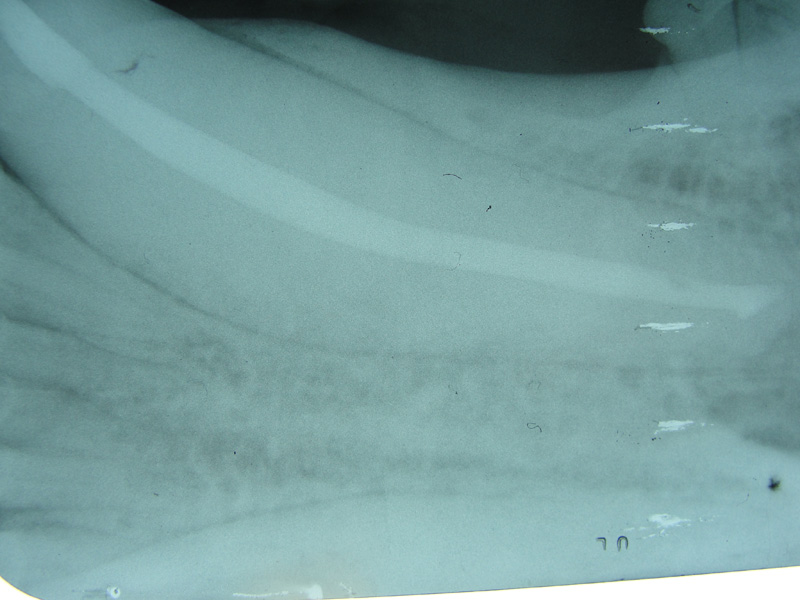

Bongo “Ira” diagram of how intermedullary pins were placed to reduce fracture.

Bongo “Ira” Radiograph of remaining pins 6 months post-op.